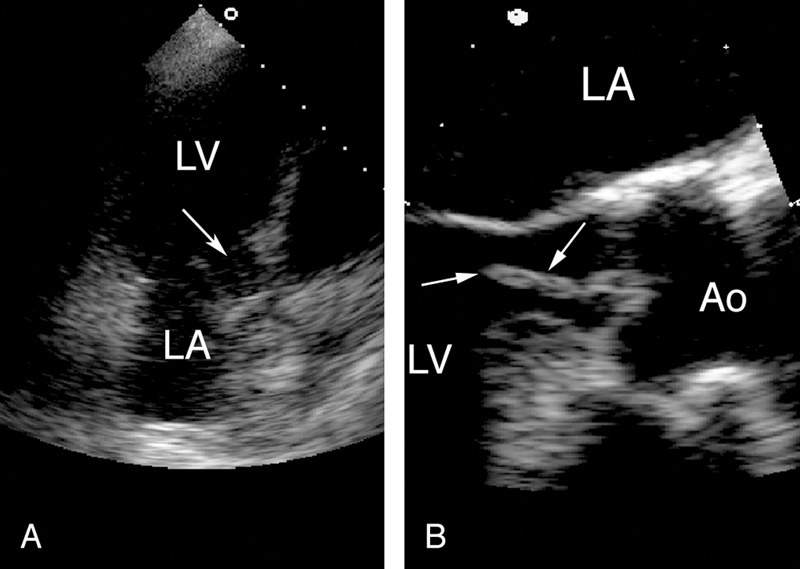

فحوصات تشخيصية لبعض امراض القلب والشرايين التاجية